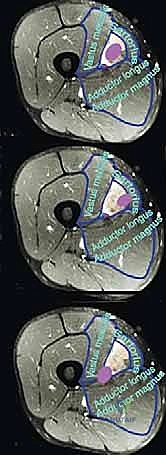

TECH FIG 1 • A. Intraoperative picture of the tumor encroaching on the vessels. The sartorius muscle has been disconnected distally to improve exposure.

* Frozen Section Analysis: Once the tumor is resected, we will send the fibrous sheath surrounding the vessels for frozen section analysis. This is critical to rule out microinvasion and confirm negative margins.

* Surgical Directive: "Pathology, please. We're sending the fibrous sheath overlying the vessels for frozen section. We need to confirm this sheath is free of tumor."

* Vascular Preservation: Vascular resection is typically not required for Type 1 tumors.

TECH FIG 1 • B. The tumor has been resected with the thick fascial sheath that lines the vessels and with the muscle and fascia from which it arises. V Med M , vastus medialis muscle; Add Mag , adductor magnus muscle; SF A&V , superficial femoral artery and vein.

* Vessel Sheath: Even if the tumor doesn't grossly invade the vessels, the fibrous sheath surrounding them, if in intimate proximity, should be resected en bloc with the tumor and sent for frozen section to ensure clear margins.

TECH FIG 1 • C. Soft tissue reconstruction with a gracilis muscle transfer affords good coverage of the vessels of the sartorial canal and is crucial. The distal end of the gracilis muscle is disconnected and rotated anteriorly. The muscle is then spread like a fan and reattached anteriorly.

* If the sartorius muscle was preserved, it can also be used to cover the defect.

rius muscle or, if that was excised with the tumor, the adjacent gracilis muscle. A gracilis muscle transfer ( TECH FIG 1C ) is done by dissecting the distal end of the gracilis free and rotating the muscle anteriorly to cover the canal. This provides good soft tissue coverage.